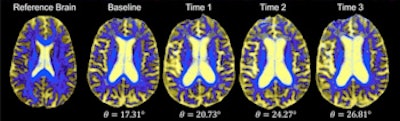

DSEG images for axial brain slices of SVD patients. Images in the SVD brain are shown over three time points with DSEG Θ angle scores for microstructure changes. Increases in Θ show substantial DSEG changes in brain microstructure over time with increasing brain damage. © 2017 The Authors (CC BY-NC-ND 4.0).

The developed methodology utilizes a diffusion tensor image segmentation (DSEG) technique, combining several MRI-detectable SVD markers to produce a sensitive singular score for disease severity and brain damage. This enables monitoring of alterations in brain microstructure over time via a single angular measure -- DSEG Θ.